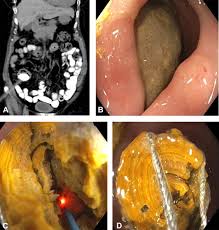

Bowel perforation occurs when a hole develops in the wall of the intestine. This can happen due to a variety of factors, including trauma, infection, and certain medical conditions. In the case of ESWL, bowel perforation is thought to be caused by the shock waves themselves.

The shock waves used in ESWL are powerful enough to break up kidney stones, but they can also damage nearby tissues. If the shock waves are focused on the wrong area, they could potentially cause a bowel perforation. However, this is a very rare occurrence.

ESWL is a generally safe procedure, and the risk of bowel perforation is very low. Doctors are very careful to avoid targeting the bowel during the procedure. They use imaging techniques to ensure that the shock waves are focused on the kidney stones.

Bowel perforation is a serious complication, but it’s important to remember that it’s very rare. If you’re concerned about the risks of ESWL, talk to your doctor. They can explain the risks and benefits of the procedure and help you decide if it’s the right treatment for you.